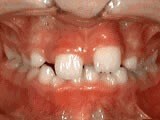

Patient’s parents were concerned about both aesthetics and the health of the erupting permanent teeth when they brought him to the orthodontist at age eight. The lower front teeth were crowded and touching the palate, and the upper front teeth were extremely displaced from their normal positions. After 12 months of Phase-One treatment with an expander and partial braces, patient’s appearance and dental function were vastly improved.